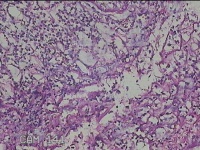

左侧腋下结节

性别

女

年龄

46岁

临床诊断

皮下结节

一般病史

发现左侧腋下一结节1周,伴局部隐痛不适,无发热。

标本名称

大体所见

灰白暗红色组织1.8x1.3x0.3cm一块,表面带梭形皮肤1.8x0.5cm,皮下见结节1.2x0.8cm,切开结节呈实性,切面灰白淡黄色,质软。

炎症性病变。